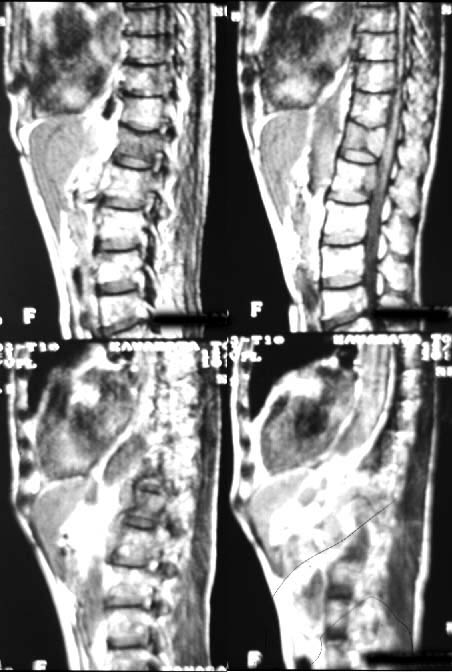

| 第196回定例研究会(1997.6) 骨シンチ『異常集積の少ない骨転移』 | 神奈川県立がんセンター | 小野 慈 |

| 第196回定例研究会(1997.6) 骨シンチ検査の基礎講座 | 神奈川県立循環器呼吸器病センター | 大島 正行 |

(2)compartment解析に関しては代表的なものは、1-compartment model(秀毛らの非線形model(Fig.3)に始まるが、篠原が報告した如く線形modelでの短時間に演算可能な方法でも実用的であった。Veraらが唱えた3-compartment modelは採血を伴うmodel式を利用しており、やや煩雑さを伴っている。河らが提唱した5-compartment modelは複雑な計算式を必要としているが、肝最大除去率(Rmax)を算出可能である。(Fig.4)病的 hotなし。 | 第12胸椎に骨溶解像。 | 第12胸椎に 低信号域。 |

![]() | ![]() | ![]() |

| ・全身シンチ | ||||

| コリメータ | 収集マトリックス | ピクセルサイズ | 収集条件 | 撮像方向 |

| mm/Pixel | (スキャンスピード) | |||

| LEHR | 256×1024 | 2.0 | 10〜15cm/min | ANT,POST |

| 512×2048 | 1.0 | |||

| ・部分シンチ | ||||

| mm/Pixel | (カウントorタイム) | |||

| LEHR | 512×512 | 0.6〜1.0 | 1000K(8分) | 異常部位多方向 |